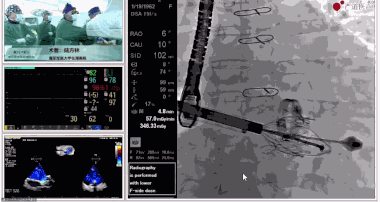

▲瓣膜植入后釋放的過程

▲瓣膜植入后三維超聲影像

▲瓣膜植入后右心室造影

在手術直播中瓣膜植入過程不到10分鐘,手術獲得圓滿成功,充分體現徐志云、陸方林團隊技術精湛,團隊協作默契及器械的優越性。